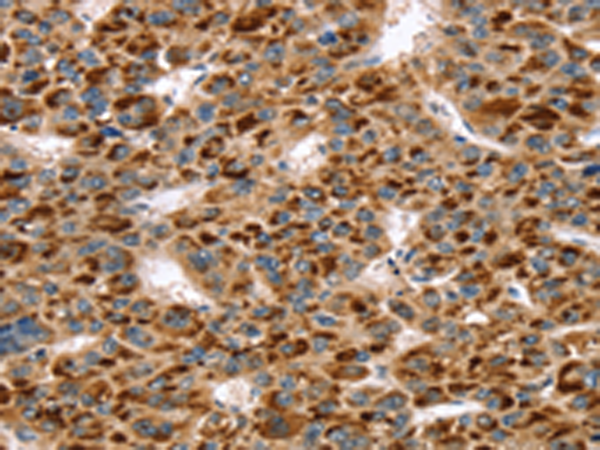

分类: 科研抗体货号: P01830别名: Mvp1应用: WB,IHC反应种属: Human, Mouse

分类: 科研抗体货号: P01824别名: SNO; SnoA; SnoI; SnoN应用: WB,IHC反应种属: Human, Mouse

分类: 科研抗体货号: P01821别名: SNAP-23; SNAP23A; SNAP23B; HsT17016应用: WB,IHC反应种属: Human, Mouse, Rat

分类: 科研抗体货号: P01882别名: TCFEB; BHLHE35; ALPHATFEB应用: WB反应种属: Human, Mouse

分类: 科研抗体货号: P01906别名: CC3; TIP30; SDR44U1应用: WB反应种属: Human, Mouse

分类: 科研抗体货号: P01874别名: EBI; TBL1; SMAP55应用: WB,IHC反应种属: Human, Mouse

分类: 科研抗体货号: P01903别名: RNF9; HERF1; RFB30应用: WB,IHC反应种属: Human

分类: 科研抗体货号: P01868别名: TAF2I; PRO2134; TAFII28; MGC:15243应用: WB,IHC反应种属: Human, Mouse, Rat

分类: 科研抗体货号: P01898别名: AFP; RNF95; ZNF173应用: WB,IHC反应种属: Human, Mouse, Rat

分类: 科研抗体货号: P01859别名: slp5应用: IHC反应种属: Human, Mouse, Rat